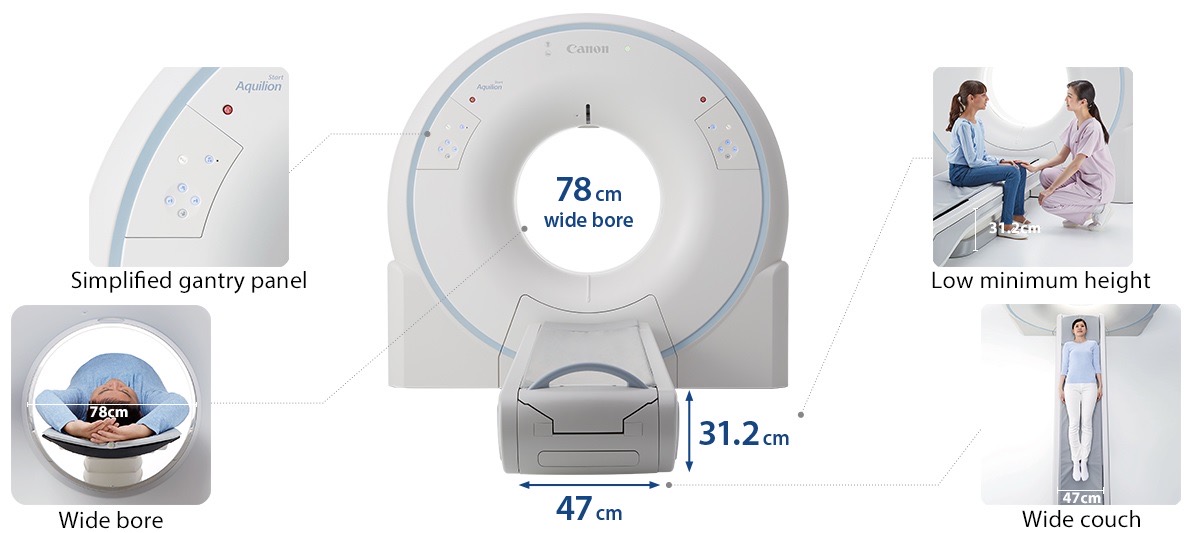

Canon, Aquilion Start, sistema de Tomografía Computada helicoidal de 16 filas de detectores y 32 cortes, para imágenes de cuerpo entero, dispone de tecnología Premium desarrollada originalmente para nuestros sistemas de TC de alta gama. Está cuidadosamente diseñado y adaptado a los requisitos cambiantes de las organizaciones de atención médica, incluida la necesidad de flujos de trabajo más rápidos, accesibilidad universal y economía sólida.

Incluye Inteligencia Artificial AiCE, tecnología avanzada de Reconstrucción de Imágenes por Aprendizaje Profundo, que ha sido entrenada para reducir el ruido y reforzar la información de señal válida, con el objetivo de entregar imágenes claras y definidas a una alta velocidad y con hasta un 82% reducción de dosis (respecto FBP). Diseñado para una atención de calidad a sus pacientes, asegurando máximo confort, experiencia de escaneo superior y la menor dosis con las mejores imágenes.